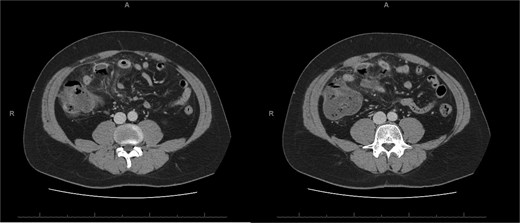

A 76-year-old female with a 3-day history of left upper abdominal pain, vomiting, and haematochezia. Her history included pulmonary embolism, multiple deep vein thromboses, with no ongoing anticoagulation, and an open partial colectomy for complicated diverticulitis a decade earlier. On admission, she was afebrile but tachycardic and showed localized tenderness in the left hypochondrium. Laboratory revealed leucocytosis with a white blood cell count (WBC) of 12 G/L, elevated C-reactive protein (CRP) of 46 mg/L, and hyperlactatemia of 2.6 mmol/l. Enhanced computed tomography (E-CT) revealed jejunal venous ischemia in the left upper quadrant, secondary to extensive porto-mesenteric thrombosis with reduced bowel wall enhancement, distention, and free intraperitoneal fluid (Fig. 1). She was managed conservatively with unfractionated heparin (UFH) with a bolus of 5000 U/l followed by 30 000 U/l/24 h (target INR 0.35–0.7), Piperacillin-Tazobactam, and bowel rest. After 48 h of monitoring in the intensive care unit (ICU), she exhibited marked biological and clinical improvement. E-CT on the third day showed restored bowel wall enhancement and stable porto-mesenteric thrombosis (Fig. 2). She was discharged on therapeutic low molecular weight heparin (LMWH) with enoxaparin sodium 120 mg every 12 h. At the 3-month follow-up, E-CT revealed near-complete thrombus resolution, without intestinal sequelae (Fig. 3).

Abdominal E-CT of the first patient at admission. The white arrows indicate extended porto-mesenteric thrombosis, while the dashed arrows reveal jejunal venous ischemia with a lack of bowel wall enhancement, bowel distension, and free fluid.